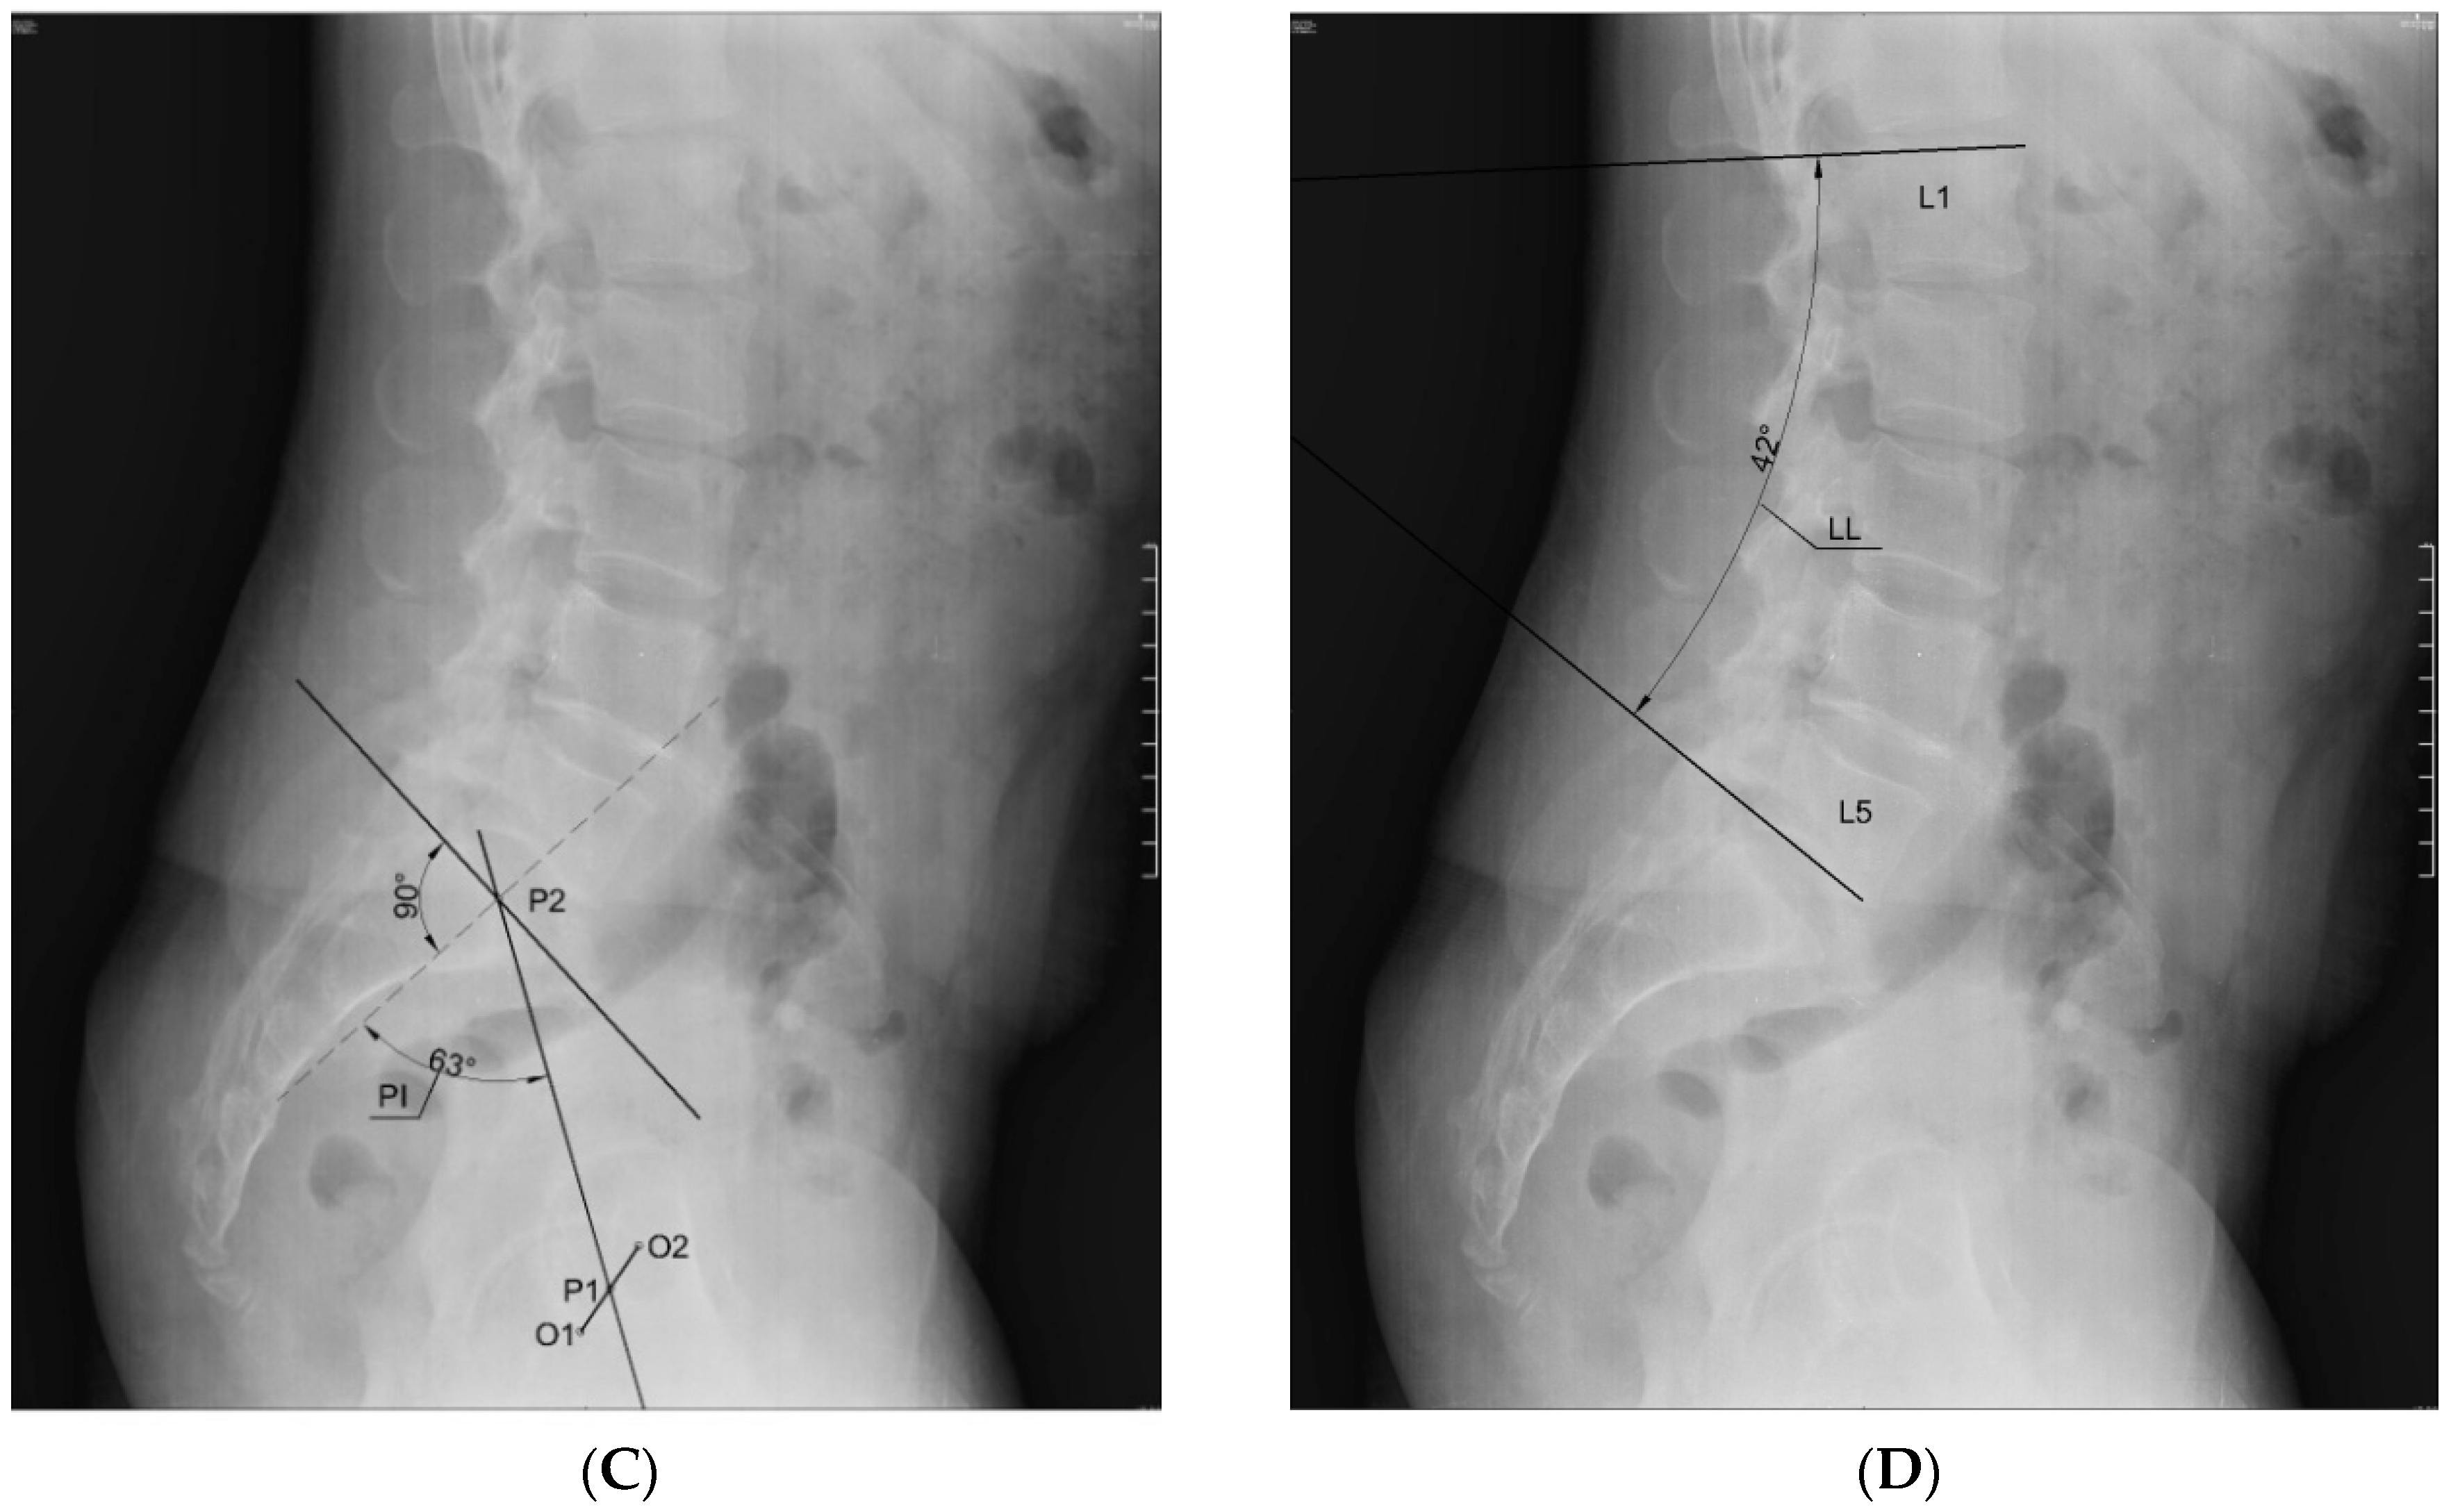

The mobility range test of the knee joints was performed first (goniometer MoVes 08-030202). The results of the test determined whether or not the candidate was included in the study. Secondly, body weight and height were measured (portable height meter Leicester Tanita HR 001, Tanita; weight measuring device Tanita BC-543, Tanita), and the BMI was calculated. In the next step, the researchers performed an X-ray in the lateral projection in standing position with the visualization of the lumbar spine, the pelvis, and the femoral heads. The subjects were asked to take a relaxed stance with their hands crossed on their chest (fists on the clavicles). If the flexion contracture occurred on the right side, the subjects were asked to position themselves with their right side to the radiation source, and if the flexion contracture occurred on the left side, they were asked to position themselves with their left side to the source of the radiation. The subjects kept their footwear for the X-ray test. If the subjects wore shoe inlays on a daily basis, the X-ray was done with them. The distance from the radiation source was 100 cm. The radiation beam was targeted at the L3 vertebra. Measurement of the angle values of indicators characterizing the position of the lumbar–pelvic complex—SS, PT, PI, and LL (Figure 1)—was established on the basis of X-ray imaging analysis. Measurements were made using AutoCAD LT 2013 software (Autodesk). The correctness of plotted angles was assessed by radiologist (MS) using the mediCAD program (mediCAD Hectec GmbH).

Figure 1. Method of plotting of the angle denoting: A—the sacral slope (SS) in the sagittal plane; B—the pelvic tilt (PT) in the sagittal plane; C—the pelvic incidence (PI) in the sagittal plane; D—the value of curvature of the lumbar spine (lumbar lordosis, LL) in the sagittal plane. Source: archive of own images.